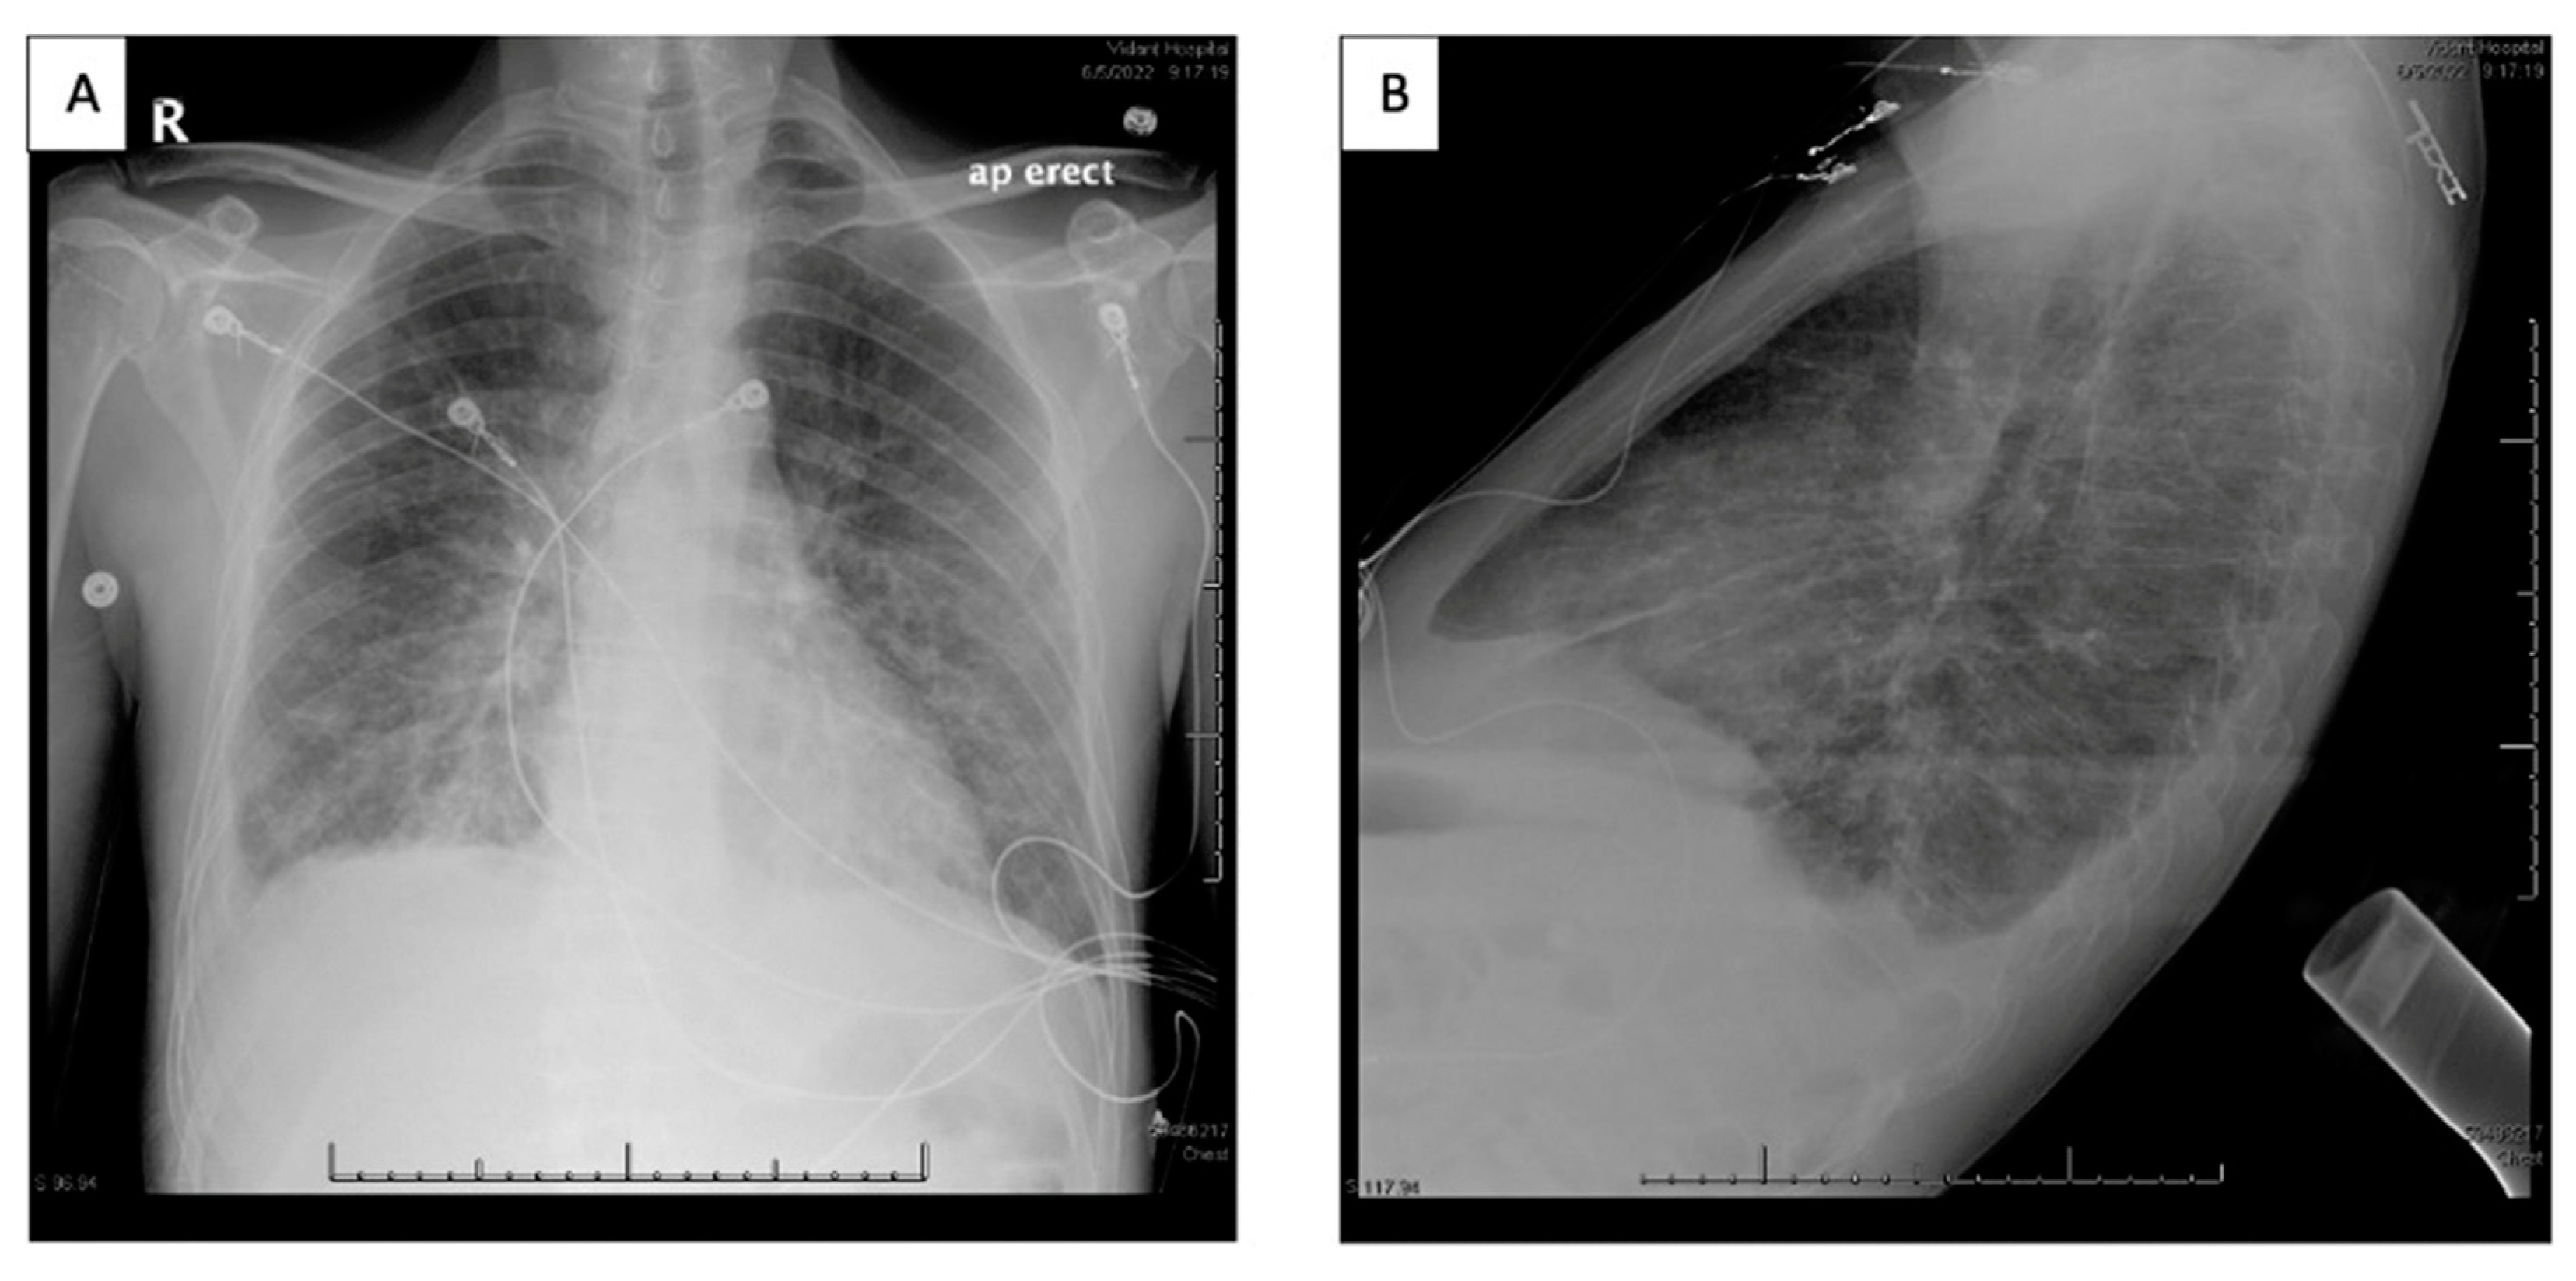

Figure 3. Chest x-ray (A: AP erect, B: Lateral) indicating predominant heterogeneous pulmonary opacities likely representing pulmonary edema and scattered atelectasis. Small right pleural effusion with trace left pleural effusion.

A 49-year-old African American male with a 20-year history of HIV, noncompliant on HAART returned for care to the HIV clinic after two years and was admitted to the hospital with complaints of worsening shortness of breath, nonproductive cough, significant unintentional weight loss and new hyperpigmented skin lesions [Figure 1, Figure 2 and Figure 3]. CD4 count was less than 100 and HAART was restarted along with TMP-SMX. Biopsy of skin lesions confirmed Kaposi sarcoma. Work-up was done for his respiratory symptoms and opportunistic infections were ruled out [Figures 4–7]. Chest imaging showed patchy and nodular ground glass infiltrates with bilateral small pleural effusions [Figures 5 and 6]. Bronchoscopy with endobronchial ultrasound, bronchoalveolar lavage and fine-needle aspiration cytology were performed due to concern for Kaposi’s sarcoma lung involvement. Findings were suspicious of Kaposi involvement, however, were atypical [hemosiderin laden macrophages]. The patient was discharged home with hematology/oncology and infectious disease follow-up as outpatient. While he was being worked up outpatient to rule out systemic involvement of Kaposi’s sarcoma, he developed a worsening left lateral foot lesion with pain and new purulent drainage and was readmitted to the hospital for concern of infection and underlying osteomyelitis. MRI of the left foot showed findings concerning for osteomyelitis. The patient received debridement with deep cultures and biopsy, which ruled out osteomyelitis and superficial wound infection. While in the hospital he was also worked up for Kaposi sarcoma systemic involvement by esophagogastroduodenoscopy and colonoscopy, which showed lesions in the esophagus, stomach, duodenum, and rectum [Figure 4 and Figure 5]. Biopsy specimen from nodular erythematous rectal mucosa returned positive for Kaposi’s Sarcoma confirming systemic involvement. Chemotherapy was initiated with liposomal doxorubicin after checking his baseline echocardiogram, which was normal.